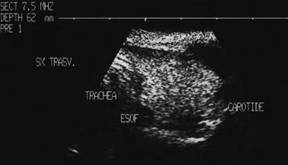

Tiroida normala

Ecostrutura omogena, normoecogena. Dimensiuni normale.

Se urmaresc rapoartele cu carotida, jugulara, muschii, traheea, esofagul.